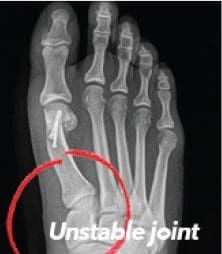

Bunions are more than a simple bump on the side of the foot — they are complex, three-dimensional deformities caused by an unstable joint at the base of the big toe. While many people assume a bunion can simply be “shaved off,” traditional procedures often fail to correct the true source of the problem. This is why bunions commonly return, leaving nearly 1 in 3 patients dissatisfied with prior surgical results.

Unlike traditional bunion surgery that cuts and shifts the bone, Lapiplasty® uses advanced, precision instruments to rotate the entire deviated bone back into alignment. Titanium plating technology then secures the correction at the root of the deformity, stabilizing the joint and helping prevent recurrence.